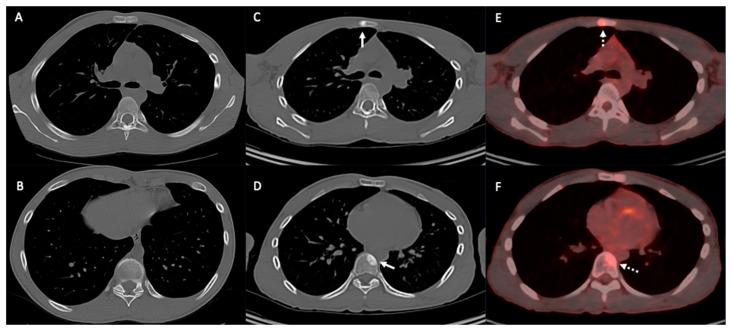

Osteosarcoma, a primary bone malignancy in children and adolescents, frequently metastasizes to the lungs, contributing significantly to morbidity and mortality. At diagnosis, 15-20% of patients present with detectable lung metastases. Chest computed tomography (CT) is vital for the early detection and monitoring of these metastases. Lung involvement typically presents as multiple nodules of varying sizes and can include atypical features such as cavitation, cystic lesions, ground-glass halos, intravascular tumor thrombi, and endobronchial disease. Pleural metastasis often occurs alongside pulmonary disease, and complications like spontaneous pneumothorax may arise. Additional findings may include thoracic lymphadenopathy, cardiac tumor thrombus, and chest wall deposits. Familiarity with these imaging patterns is essential for radiologists to ensure timely diagnosis and effective management. This review highlights the critical role of chest CT in detecting and characterizing osteosarcoma metastasis.

骨肉瘤是儿童和青少年常见的原发性骨恶性肿瘤,常转移至肺部,对发病率和死亡率有显著影响。在诊断时,15%至20%的患者出现可检测到的肺转移。胸部计算机断层扫描(CT)对于这些转移灶的早期检测和监测至关重要。肺部受累通常表现为大小不一的多个结节,可包括一些非典型特征,如空洞形成、囊性病变、磨玻璃晕、血管内肿瘤血栓和支气管内病变。胸膜转移常与肺部疾病同时发生,可能出现自发性气胸等并发症。其他表现可能包括胸内淋巴结肿大、心脏肿瘤血栓和胸壁转移灶。放射科医生熟悉这些影像学表现对于确保及时诊断和有效治疗至关重要。本综述强调了胸部CT在检测和鉴别骨肉瘤转移方面的关键作用。